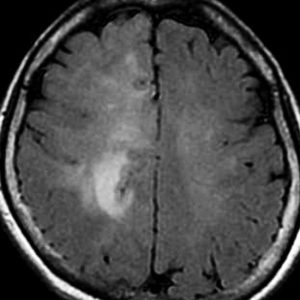

左側頭葉のびまん性星細胞腫です。左側のT1強調ガドリニウム像ではほとんど腫瘍は見えません。真ん中のT2強調画像でも見づらいです。右側のフレア画像で白くにじんでいるところに腫瘍があります。どこまでが腫瘍の境界なのかがはっきりしない腫瘍です。左の海馬(記憶の中枢)を侵し,とてもゆっくり大きくなるタイプで,この患者さんは10年以上治療をしないで経過を見ています。全摘出できない星細胞腫グレード2です。

フレア画像です。左上前頭回の星細胞腫ですが,境界がとてもはっきりしていて限局性 localized single gyrus glioma です。びまん性 diffuseには見えません。IDH1の変異があり,1p/19qの欠失はないので星細胞腫グレード2です。上の例とは全く違う臨床像を示しますが,分子病理でも区別はつきません。頑張って早めに全摘出して治してしまった方がいいタイプです。再発を避けるために,supratotal resectionと言って,周囲の正常脳組織も10mmくらい余分に摘出します。